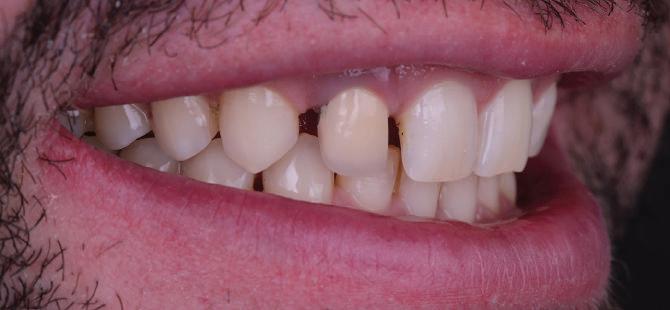

7Dental Tribune Bulgarian Edition / октомври 2022 г. Преди лечението Фиг. 1 Фиг. 4 Фиг. 7 Фиг. 10 Фиг. 13 Фиг. 16 Фиг. 17 Фиг. 18 Фиг. 19 Фиг. 20 Фиг. 11 Фиг. 14 Фиг. 12 Фиг. 15 Фиг. 8 Фиг. 9 Фиг. 5 Фиг. 6 Фиг. 2 Фиг. 3

Пациентът постъпи в клиниката с молба за тотална рехабилитация на усмивката. Той не харесваше централ ните си резци, които според него бяха твърде къси и квадратни. Имаше раз стояние от медиално и дистално на латералните му резци. Друго сериоз но оплакване бе свързано с металоке рамичната корона на зъб 12, която бе жълтеникава и неестетична, като цяло не харесваше вида на венците си и както самият той се изразяваше, „вижда се прекалено много от венците при усмивка“.

Пациентът постъпи в моята клини ка с наличие на темпоромандибуларен дисфункционален болков синдром, едно странно изместен диск с редукция в дяс ната става, клас II, подклас 2, тесни гор на и долна челюст със струпване, дъл бок овърбайт

Пациент: 30 г., мъж Първо посещение: 02.08.2018 г. Основни оплаквания: Лицева болка, главо болие и болка в дясната темпоромандибу ларна става, естетични съображения РАБОТЕН ПРОТОКОЛ:

диагностика терапия със сплинт ортодонтска рехабилитация диагностична реоценка вертикален размер на оклузията –диагностичен восъчен моделаж протетична рехабилитация работа в зъботехническата лабора тория диагностична реоценка поддръжка

СПИСЪК С ПРОБЛЕМИ:

тясна зъбна дъга – горна и долна струпване във фронта – в горна и долна челюст вертикален излишък в максилата, водещ до скелетна гингивална усмивка недобри амалгамени и композитни обтурации наличие на мъдреци 18, 38, 48 – стръм на